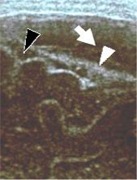

При УЗИ на следующий день (26 часов после травмы), эхо-признаки гемоперитонеума сохранялись,

признаки дефекта паренхимы печени оставались без выраженной эхографической динамики,

одновременно, были выявлены значительные изменения эхографической картина со стороны

почек. При исследовании в В-режиме, на границе медуллярного и кортикального слоев паренхимы,

у основания пирамид, появился неширокий (2-3мм) гиперэхогенный "ободок", предположительно,

соответствующий отложению продуктов тканевого распада на юкста-медуллярном уровне (рис.2).

Рисунок 2. Тот же ребенок, осмотр

через 26 часов после травмы.

| а - при сканировании в В-режиме сохраняются эхо-признаки дефекта

паренхимы правой доли печени значительных размеров. |

б - сканирование в цветовом и энергетическом допплеровском режимах

соответственно. Сохраняется бессосудистая зона в проекции дефекта паренхимы. |

в - при сканровании в В-режиме в проекции малого таза определяется наличие значительного

количества гипо- и анэхогенного компонента в брюшной полости (гемоперитонеум). |

| г - правая почка, сканирование в В-режиме, латеральный доступ.

Топография и размера почки не изменены, контуры ровные, структуры дифференцированы.

У основания пирамид, в юкста-медуллярной зоне, определяется гиперэхогенные "ободки"

шириной до 2-3 мм. |

д - правая почка, латеральный доступ, дуплексное допплеровское

сканирование в цветовом режиме. Интраренальный сосудистый рисунок сохранен во

всех отделах паренхимы. |

е - допплерография в импульсном режиме на уровне интерлобарной

артерии (правая почка). Скоростные и резистивные показатели кровотока - в пределах

нормы (Vmax = 0,24 м/сек, RI = 0,78). |